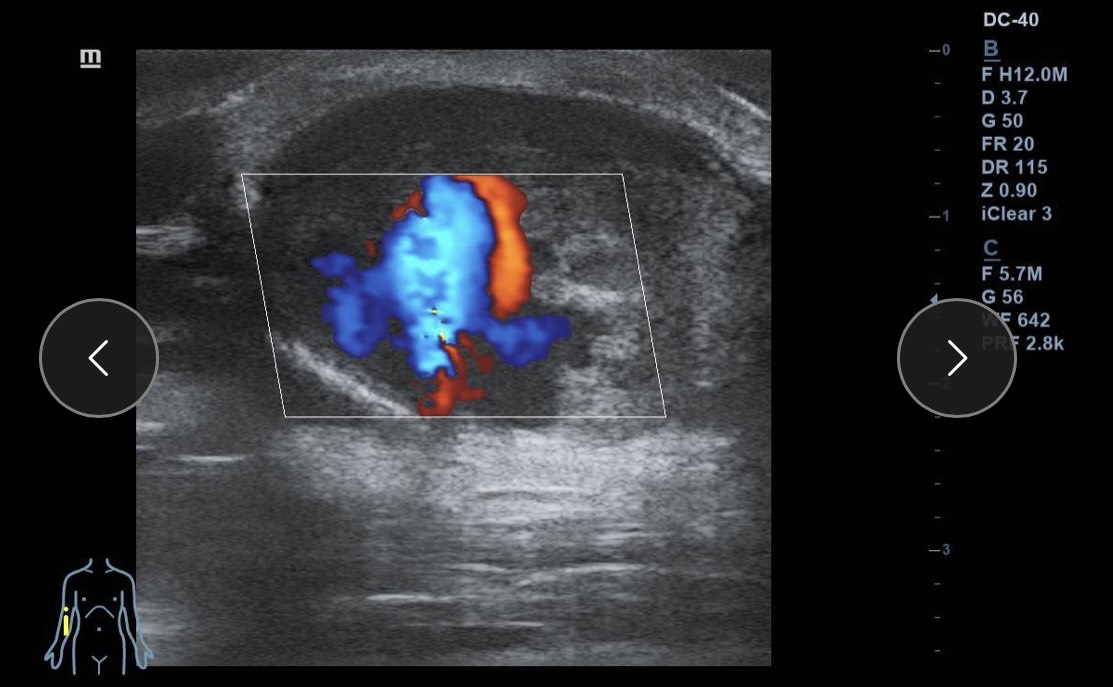

Ante la sospecha de patología vascular, se realiza ecografía clínica en la consulta.

Hallazgos ecográficos

Ecografía Doppler: dilatación aneurismática sacular de la arteria braquial (3 cm), bien delimitada, con trombo mural no oclusivo y flujo turbulento. Flujo arterial proximal y distal conservado. Sin signos de rotura ni hematoma adyacente.